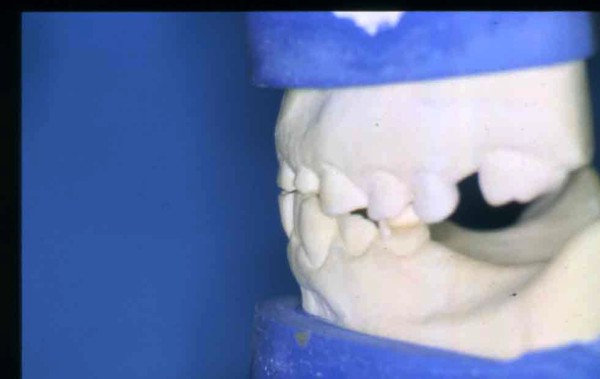

APRECIACIONES DIAGNÓSTICAS EN BASE A LA APERTURA MENTAL DEL CLÍNICO FRENTE A LO QUE EL PACIENTE PROPONE EN MUCHAS OCASIONES , LA DEMANDA DE LOS PACIENTES NOS INCLINAN A FOCALIZAR NUESTRA ATENCIÓN EN LAS PIEZAS DE LAS CUALES EL ENFERMO SE QUEJA. PACIENTE SEXO FEMENINO, 55 AÑOS, SE PRESENTA A LA CONSULTA DERIVADA POR COMPAÑERO GENERALISTA, QUIEN LLEVA MESES PROCEDIENDO A LA «DESINFECCIÓN» DE UN PRIMER PREMOLAR IZQUIERDO, EL QUE SE PRESENTA ABIERTO EN SU CONDUCTO EN EL AFÁN DE PERMITIR EL ESCAPE DE GASES DE UNA GANGRENA PULPAR. A LA INSPECCIÓN CLÍNICA SE OBSERVAN FACETAS PARAFUNCIONALES DE TERCER GRADO , ASINTOMÁTICAS, CON EVIDENTES DIFICULTADES MASTICATORIAS Y ESTÉTICAS , FALTA TOTAL DE SUS MOLARES INFERIORES, Y ADELANTAMIENTO PRONUNCIADO DE SU MANDIBULA, LA QUE CUESTA MANIPULAR DEBIDO A LA SITUACIÓN DE ESPASMO DE CASI TODA SU MUSCULATURA GNATICA. SE ESTUDIA EL CASO RADIOLOGICAMENTE, Y SE RELAJA EL SISTEMA MEDIANTE LAM. DE LONG REALIZANDO UN MONTAJE EN LA ORC OBTENIDA. NO SATISFECHOS CON EL RESULTADO, CONFECCIONAMOS UN JIG DE LUCIA, EL QUE DEJAMOS EN BOCA TODA UNA NOCHE, AL CABO DE LA CUAL REALIZAMOS UN NUEVO REGISTRO REALIZAMOS UN ENCERADO RÁPIDO DEL CASO, Y CONFECCIONAMOS UNA ESTRUCTURA OCLUSAL PLASTICA, QUE ADEMÁS REPONGA EL ASPECTO ESTÉTICO PERDIDO (FÉRULA DE RELAJACIÓN DE COMPONENTE ESTÉTICO), LO QUE PERMITE AL ENFERMO LUEGO DE DOS DÍAS DE USO, NO SOLO CORROBORAR LA COMODIDAD MASTICATORIA Y LA FALTA DE SÍNTOMAS MUSCULARES, SINO TAMBIÉN OBSERVAR APROXIMADAMENTE LA DIFERENCIA ENTRE LA SITUACIÓN INICIAL Y LO QUE PUEDE LOGRARSE MEDIANTE EL TRATAMIENTO. EL PACIENTE ADVIERTE LA MEJORÍA DE LA SITUACIÓN. ACEPTADO POR PARTE DEL MISMO EL TRATAMIENTO SUGERIDO, CREAMOS UN JUEGO COMPLETO DE PROVISORIOS EN BASE AL ENCERADO, Y PROCEDEMOS A TRATAR LA INFRAESTRUCTURA, QUE CONSISTE EN LAS ENDODONCIAS, SUS REFUERZOS A PERNOS DE ORO, LOS ASPECTOS PERIODONTALES DEL CASO, Y DOS IMPLANTES INFERIORES CON TÉCNICA SEMISUMERGIDA ,DE 5 MM DE ANCHO POR 12 DE LONGITUD, CON ANILLO DE ZIRCONIO , A LA ESPERA DE OSTEOINTEGRACIÓN, TRANSCURREN TRES MESES EN EL USO DE UNA NUEVA OCLUSIÓN CONSTITUIDA POR LOS PROVISIONALES, SEGÚN EL ENCERADO, QUE SE REALIZÓ SIGUIENDO LOS CÁNONES DE UNA OCLUSIÓN ORGÁNICA. COMPROBADA LA EFICACIA DE LA NUEVA SITUACIÓN, CON SUS DISCLUSIONES LATERALES Y POSTERO ANTERIORES CORRECTAS, CARECIENDO YA DE SINTOMATOLOGÍA MUSCULAR (SIN MIALGIAS, SIN MIOSITIS, Y CON UN GRADO DE APERTURA DE 4,50 CM), Y SIN SIGNOS EVIDENTES DE DESGASTE SOBRE EL MATERIAL DE LOS PROVISORIOS, ES DECIR: VERIFICANDO QUE EL PACIENTE YA NO BRUXA, VERTICALIZANDO EL CICLO MASTICATORIO /OTORGANDO ORC/ DIMENSIÓN VERTICAL /PROTEGIENDO A LAS PIEZAS `POSTERIORES DE IMPACTOS LATERALES RECIEN ENTONCES , MONTAMOS EN ARTICULADOR SEMI AJUSTABLE LOS MODELOS DE TRABAJO DEFINITIVOS. CONFECCIONAMOS ENTONCES LAS COFIAS INFRA PORCELANA, EN PORCELANA DE ALTA DENSIDAD EN EL SECTOR ANTERIOR Y EN ORO GALVÁNICO PARA EL SECTOR POSTERIOR PARA LUEGO COMPLETAR LA GUIA ANTERIOR , VERIFICANDO LA ALTURA DE LOS INFERIORES RESPECTO DEL LABIO INFERIOR Y CORROBORANDO LOS PUNTOS DE CONTACTOS INTER CANINOS, QUE CENTRALIZAN LA MANDIBULA Y VERTICALIZAN EL CICLO MASTICATORIO Y LAS DISCLUSIONES CANINAS QUE OTORGARÁN PROTECCIÓN A LOS SECTORES POSTERIORES. POSTERIORMENTE CHEQUEAMOS LA DISCLUSIÓN EN PROPULSIVA DE LA GUIA ANTERIOR YA TERMINADA. FIG38 FIG39 UNA VEZ OBTENIDO UN COMANDO ANTERIOR EFECTIVO, COMO LO ES LA GUIA ANTERIOR CON TODOS SUS COMPONENTES, PROCEDEMOS A REALIZAR LAS TABLAS PREMOLAR / MOLAR DE AMBOS LADOS Y OBSERVAMOS QUE LOS PUNTOS INTEROCLUSALES DE CONTACTO SEAN SUFICIENTES Y CUMPLAN SU OBJETIVO DE OTORGAR ESTABILIDAD MESIO DISTAL Y VESTÍBULO LINGUAL. TRANSCURRIDO UN AÑO DE FINALIZADO EL TRATAMIENTO, REALIZAMOS UN CHEQUEO POST OPERATORIO DEL CASO, EN TODOS LOS PARÁMETROS ANTERIORMENTE MENCIONADOS, Y OBSERVAMOS LA ABSOLUTA ESTABILIDAD DEL MISMO EN TODOS SUS NIVELES Y TEJIDOS.